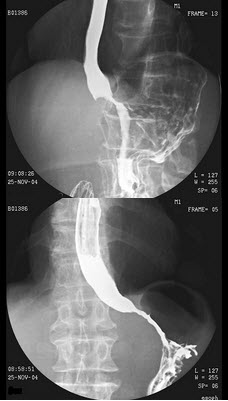

89、多项选择题

女,49岁,进食上腹痛,腹部肠胀气近2天,今肛门已排气,大便已解,结合图像,最可能的诊断为()

A.正常表现

B.慢性胃炎

C.胃溃疡

D.球部溃疡

E.胃粘膜脱垂

点击查看答案